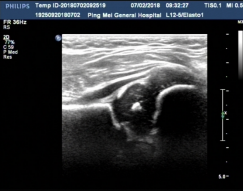

5、新生兒及小兒超聲

開展了新生兒肺臟及顱腦超聲檢查、小兒髖關(guān)節(jié)超聲檢查、性早熟超聲檢查、胎兒及小兒心臟超聲檢查等,積累了豐富的臨床經(jīng)驗(yàn),對于小兒腸套疊、腸扭轉(zhuǎn)、腸重復(fù)畸形、腸系膜淋巴結(jié)等疾病的超聲診斷有較高的準(zhǔn)確性。